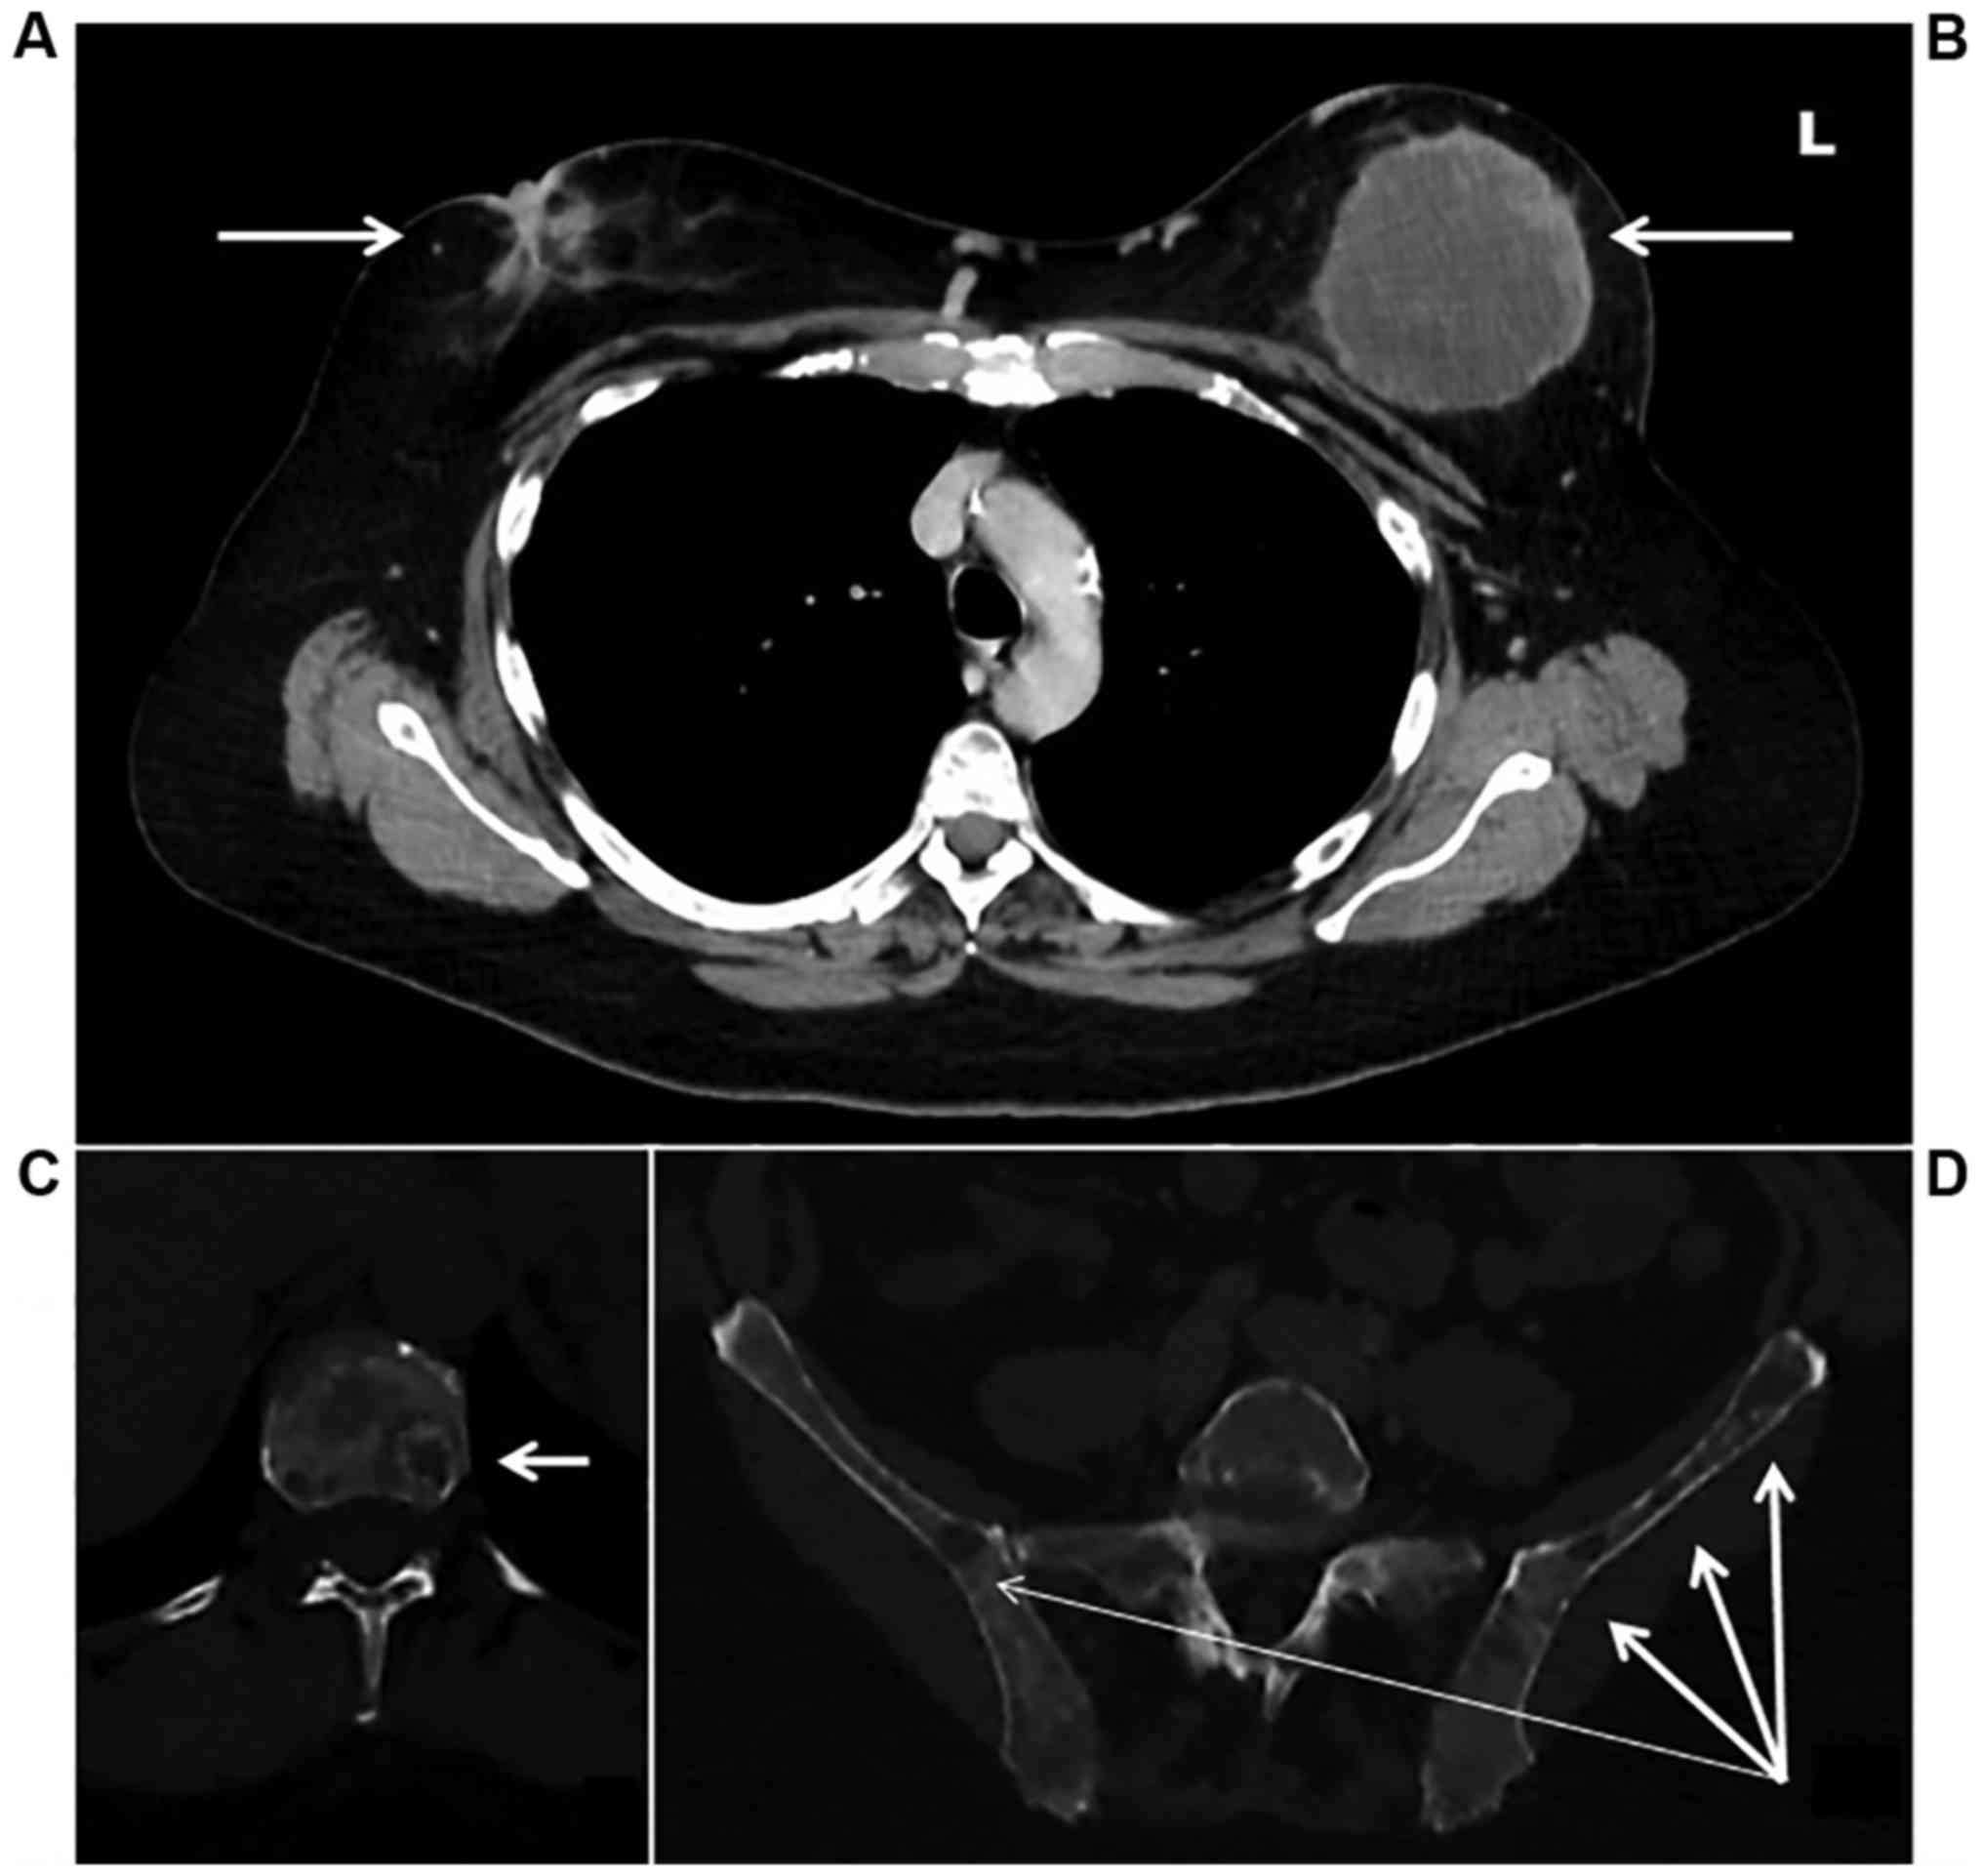

A staging computed tomography and an isotopic bone scan detected diffuse bone lesions located on the entire spine, pelvis, skull, and sternum without any visceral metastatic lesions (Fig. 4). CA 15.3 marker was measured at 2678 U/ml. Computed tomography and pelvic ultra sound did not detect ovarian lesion.

Figure 4.

Initial computed tomography. (L, left side). Chest computed tomography scan axial view showing the right breast tumor measuring 2.2 cm with cutaneous retraction (A), and the left breast tumor measuring 10 cm (B). Bone window showing vertebral bone metastasis (C) and sacral bone metastasis (D).